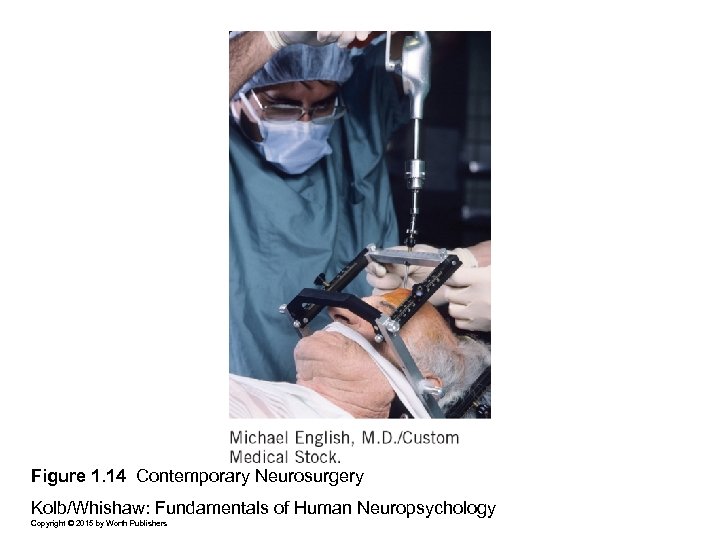

Figure 1. 14 Contemporary Neurosurgery Kolb/Whishaw: Fundamentals of Human Neuropsychology Copyright © 2015 by Worth Publishers